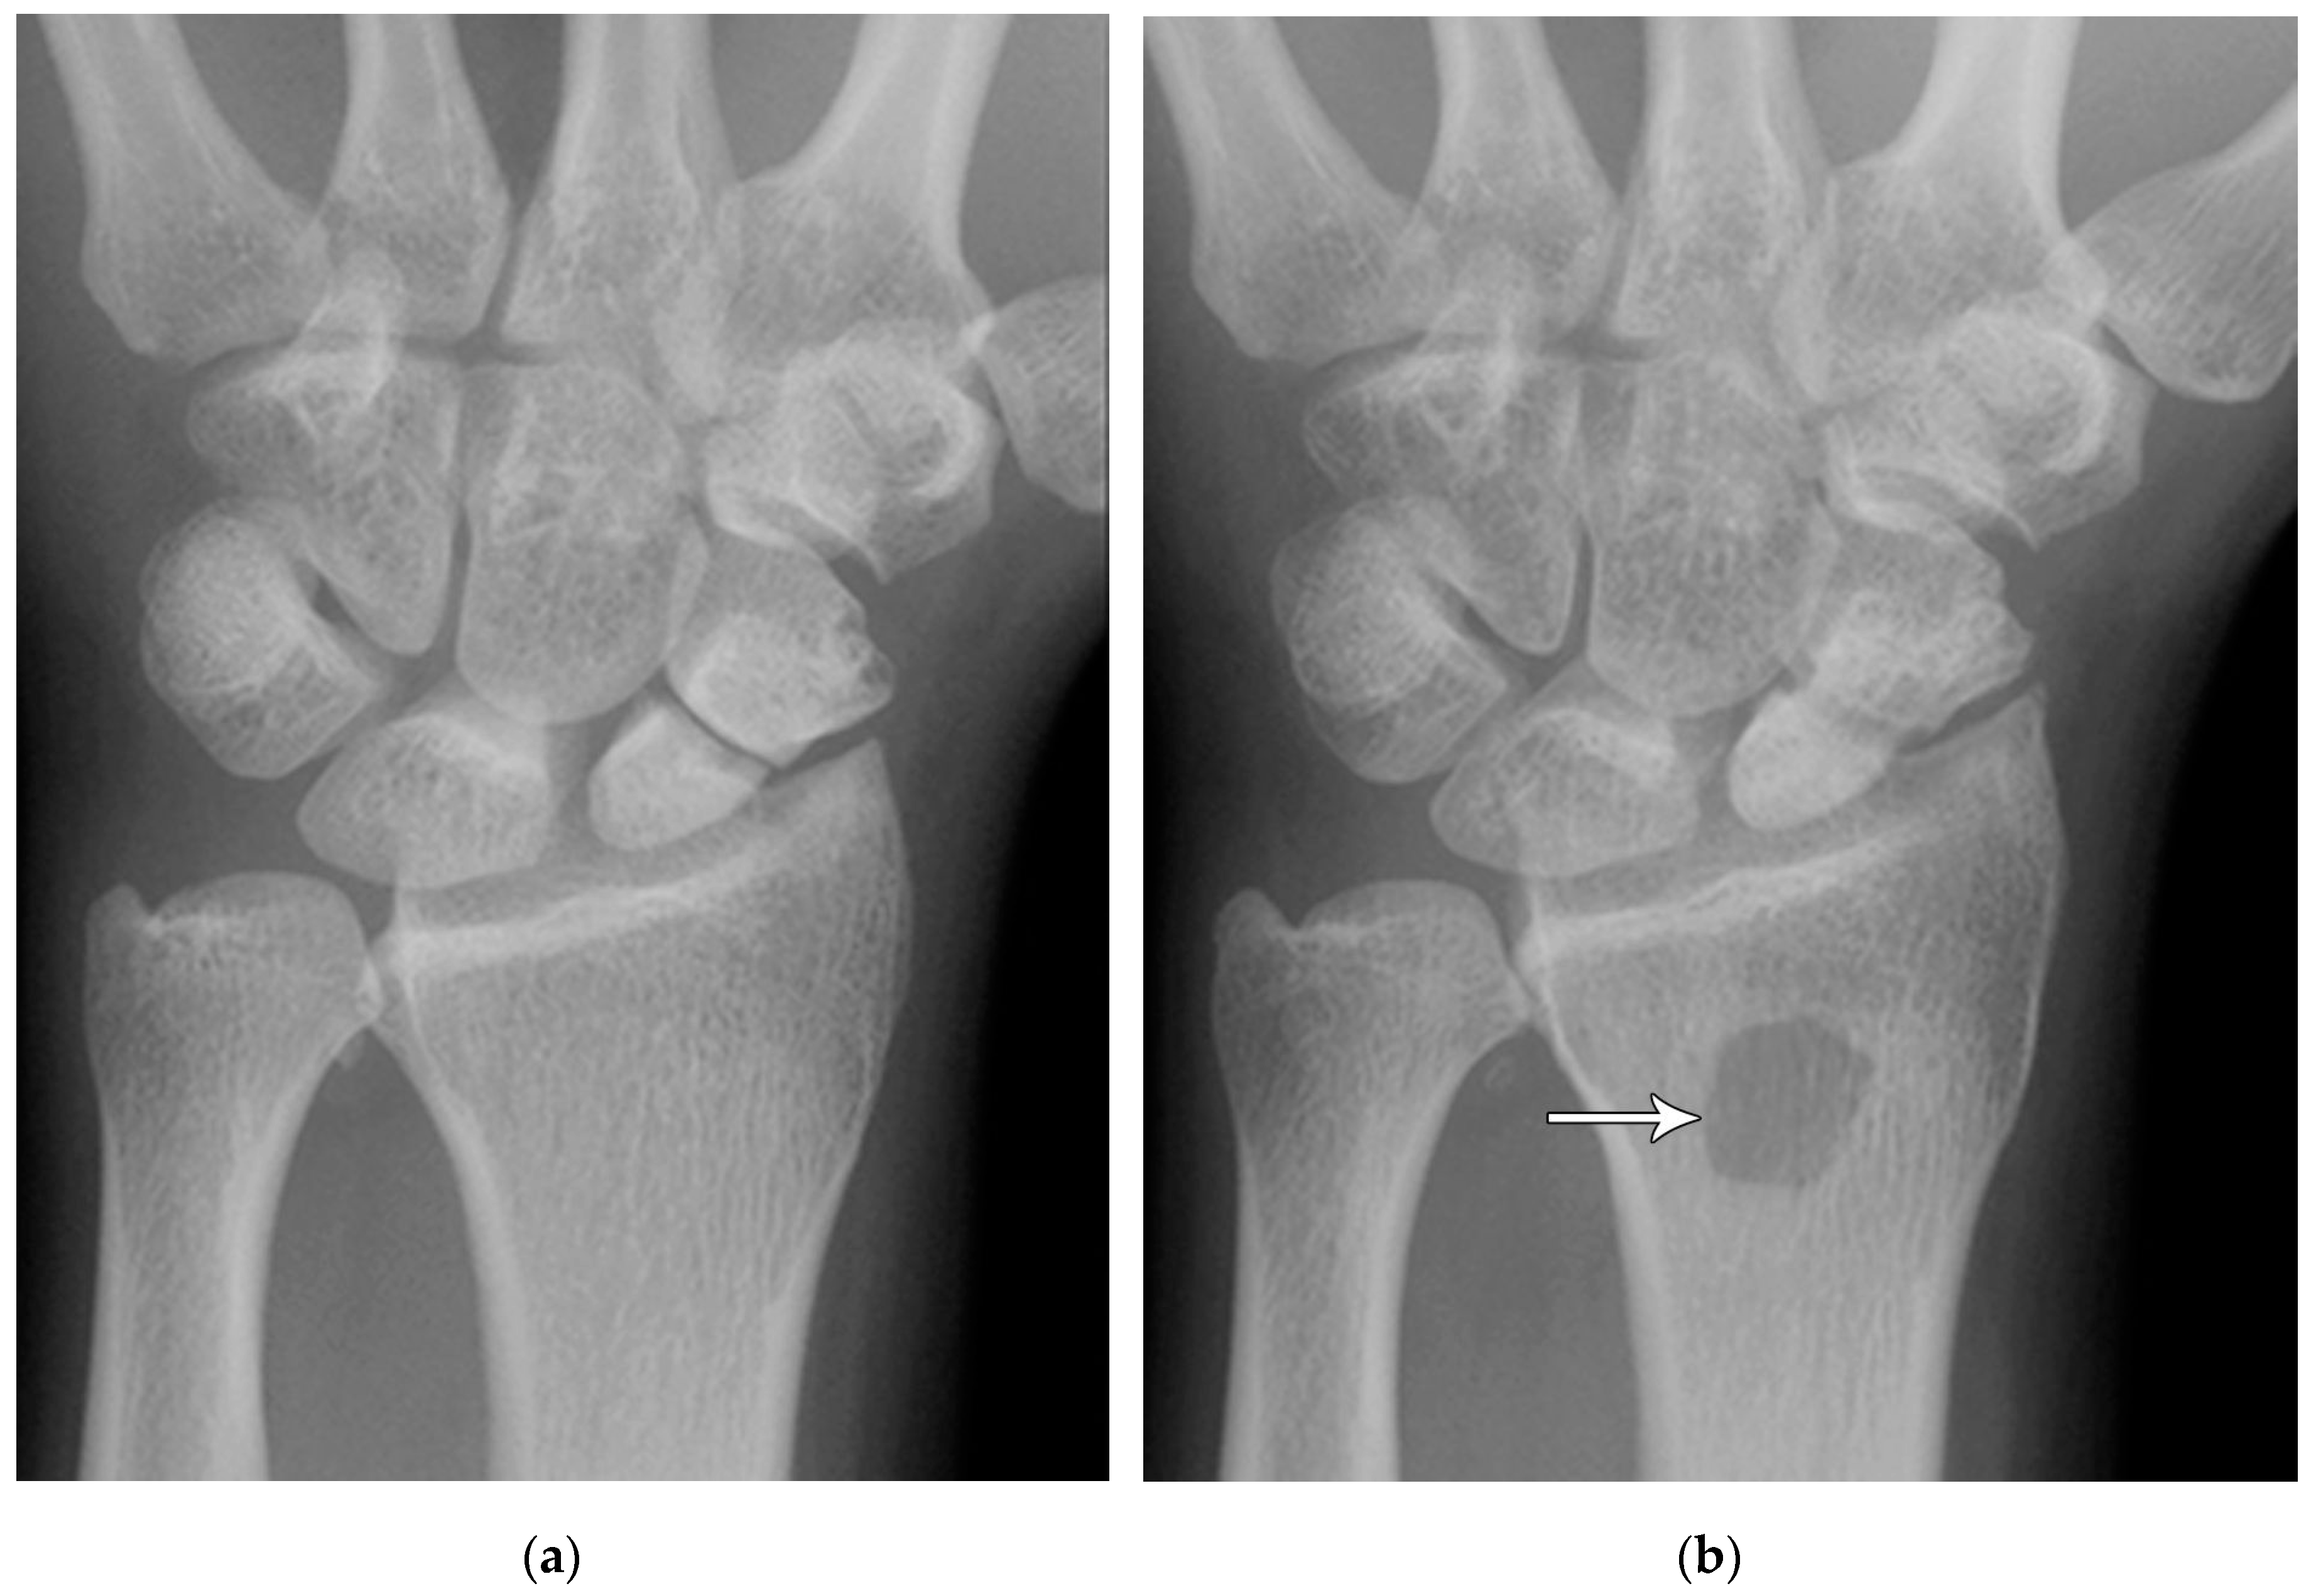

Figure 5. (a) PA radiograph showing marked sclerosis (arrow) of the proximal pole of the scaphoid after a scaphoid fracture. (b) Coronal reformatted CT in a different patient showing sclerosis (arrow) of the proximal pole of the scaphoid after a scaphoid fracture, indicating osteonecrosis.

Common scaphoid fracture complications include avascular necrosis and nonunion [10]. Avascular necrosis is a dreaded outcome resulting from loss of the proximal arterial supply due to the distal entry point of nutrient vessels. This retrograde perfusion of the proximal pole makes it vulnerable to losing its vascular supply when fractured. Sclerosis of the proximal pole indicates osteonecrosis (Figure 5). With scaphoid nonunion, biomechanical alterations contribute to rapidly progressive degenerative arthritis and instability referred to as scaphoid nonunion advanced collapse (SNAC) [16]. Nonunion occurs in 5-10% of cases and has a higher incidence with displaced fractures (Figure 6). During wrist extension, the distal scaphoid fragment rotates into flexion while the proximal scaphoid fragment extends with the lunate. The resultant abnormal contact between the distal fragment and radius begins the first stage in degenerative collapse. This progresses into the second stage as scaphocapitate osteoarthritis develops and finally to the third stage with progression to capitolunate osteoarthritis and proximal radial migration of the capitate dorsal to the lunate. Treatment of SNAC wrists, depending on the degree and severity of the osteoarthritic collapse include scaphoidectomy with four-corner arthrodesis or wrist fusion [17]. Four-corner fusion helps reduce joint pain while maintaining some range of motion, as opposed to total wrist fusion (Figure 7).